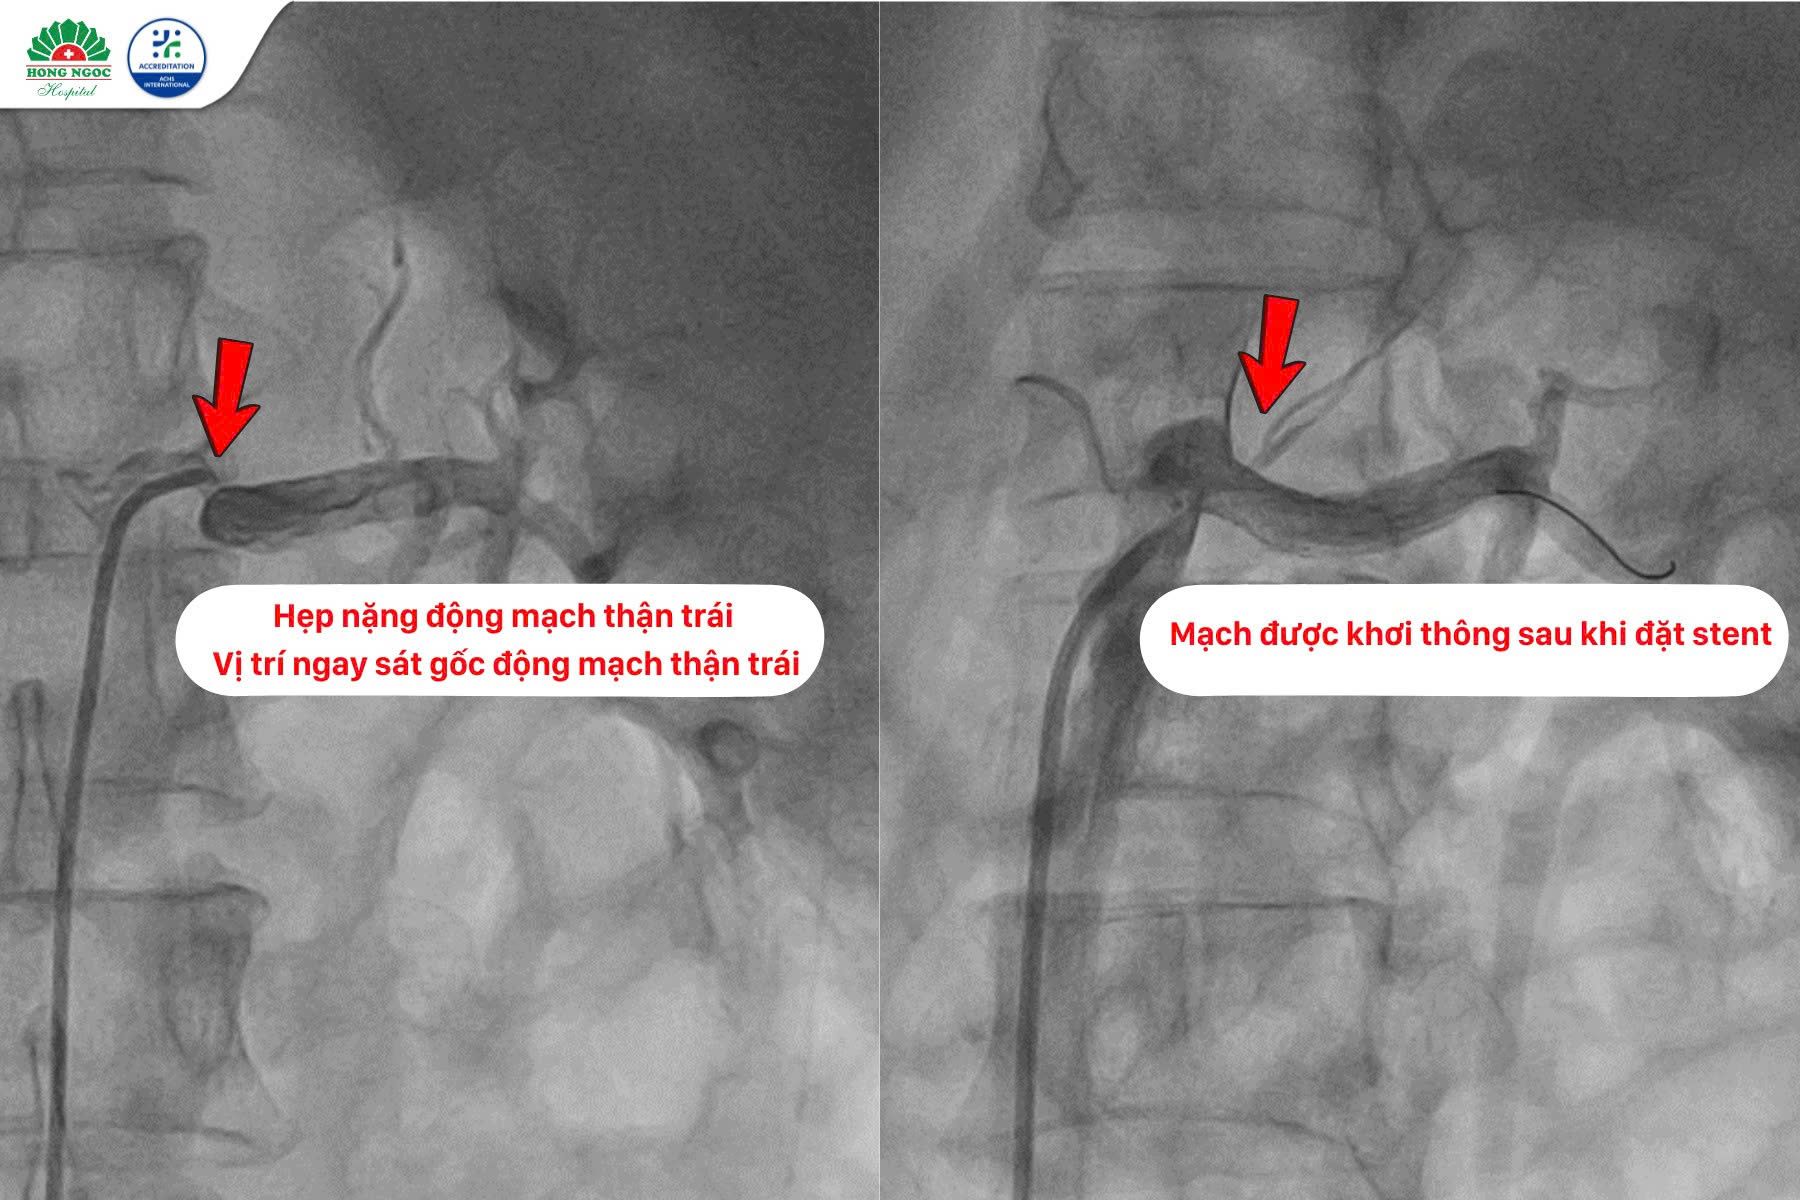

Tại BVĐK Hồng Ngọc, các bác sĩ đã tiến hành thăm khám chuyên sâu. Kết quả siêu âm Doppler động mạch thận hai bên cho thấy tổn thương hẹp nặng động mạch thận trái. Bệnh nhân được chỉ định chụp cắt lớp vi tính động mạch thận xác định rõ hơn và chuẩn bị cho kế hoạch can thiệp. Kết quả chụp cắt lớp vi tính ghi nhận có hẹp 80–90% ngay sát gốc động mạch thận trái, tổn thương dạng xơ vữa mềm, khu trú. Đây là nguyên nhân khiến huyết áp của bệnh nhân tăng cao đột ngột và khó kiểm soát.

Sau hội chẩn, các bác sĩ quyết định tiến hành can thiệp đặt stent động mạch thận. Thủ thuật được thực hiện dưới sự hỗ trợ của hệ thống máy chụp mạch hiện đại kết hợp với thiết bị siêu âm trong lòng mạch (IVUS - Intravascular Ultrasound) giúp đánh giá chính xác mức độ và đặc điểm tổn thương. Ca can thiệp diễn ra thuận lợi, stent được đặt đúng vị trí, tái thông hoàn toàn dòng chảy động mạch thận.

Hình ảnh động mạch thận trái trước & sau can thiệp đặt Stent

Đối chiếu với các khuyến cáo cập nhật hiện nay, bệnh nhân N.T. Đào có hẹp nặng động mạch thận trái (80–90%), vị trí sát gốc, tổn thương xơ vữa và biểu hiện lâm sàng là cơn tăng huyết áp cấp tính, khó kiểm soát bằng thuốc. Đây là chỉ định rõ ràng để tiến hành can thiệp.